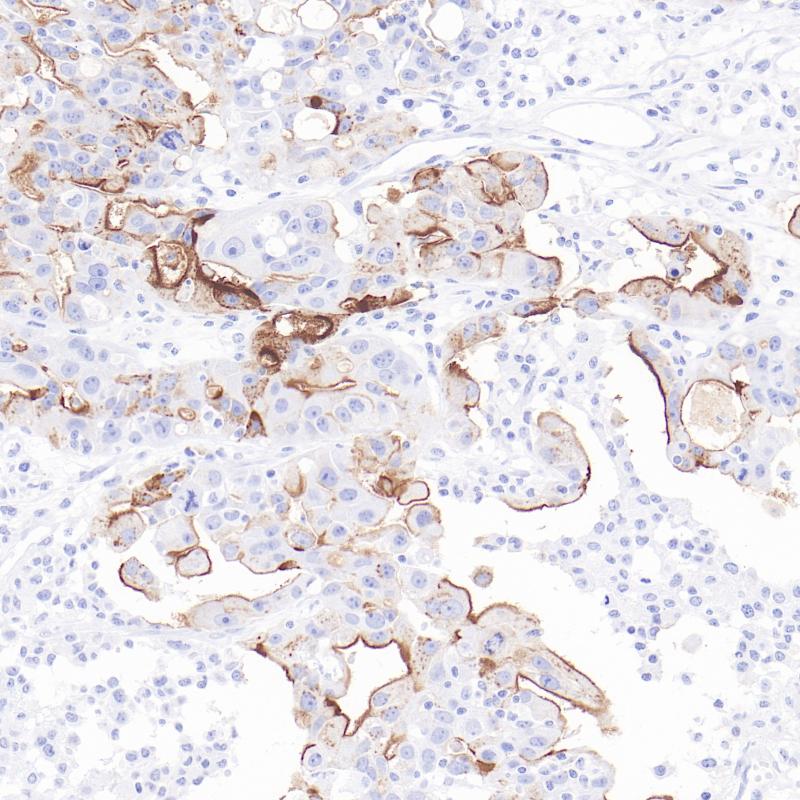

卵巢癌Claudin 6(BP6274)染色

Claudin-6是CLDN家族的一员,在上皮细胞中表达。研究表明,Claudin-6通过诱导乳腺癌细胞凋亡、抑制增殖和迁移,起到抑制恶性肿瘤的作用。Claudin6在正常组织物种中很少表达,但在肿瘤细胞中,尤其是在卵巢癌中表达量很高。

阳性对照

卵巢癌

亚细胞定位

细胞膜/细胞质